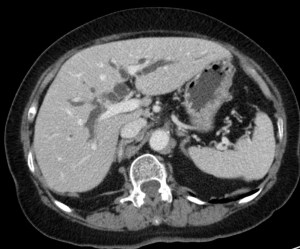

Veamos también un caso de coledocolitiasis diagnosticado por TC abdominal.